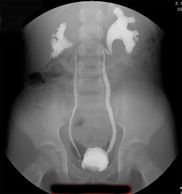

İdrar kesesindeki idrarın yukarı idrar yollarına (böbreğe doğru) kaçmasıdır.

Reflü tanısı için günümüzde kullanılan tanı yöntemleri: